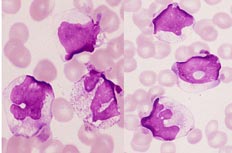

6、傳染性單核細胞增多症本病常有肝腫大和肝功能異常,但發熱比肝炎高,持續時間亦較久常有咽部疼痛、充血和內分泌物,頸及其他部位的淋巴結常腫大脾腫大及觸痛較明顯。白細胞計數正常或增多,單核細胞在0.50以上異常淋巴細胞在0.10以上,嗜異性凝集試驗陽性,抗EB病毒抗體效價有4倍以上增長或特異IGM型抗體陽性,肝活檢可見瀰漫性單核細胞浸潤及局灶性肝壞死。

7、巨細胞病毒感染正常成人受染後可出現傳染性單核細胞增多症樣的症狀、體徵和典型血象,但嗜異性凝集試驗陰性,肝臟腫痛及肝功異常較輕,肝活組織檢查可見炎性浸潤及輕度肝細胞壞死或呈小型肉芽腫及巨細胞,而在肝內找出巨細胞包涵體的機會不多。免疫抑制患者受染後可無症狀或有多數臟器受累,如肝炎、肺炎關節炎及其他多處的病變,可有發熱、白細胞減少淋巴細胞增多、異常淋巴細胞增多、肝脾腫大肌痛及關節痛。確診主要依靠從血液、尿液痰或糞便分離病毒,新鮮尿離心沉澱或口咽部分泌物塗片染色鏡檢包涵體,或雙份血清做補體結合試驗或中和試驗抗CMV效價遞升而抗EBV陰性熱為立克次體性感染,可有乏力、納差噁心J吐,大多數伴有右上腹痛及肝腫大,壓痛可不顯著;部分患者伴有脾腫大及黃疽病程中可有絮濁反應陽性及血清氨基轉移酶。鹼性磷酸酶活力上升,常類似病毒性肝炎但以下各點有助鑑別:①起病寒戰、發熱顯著,熱度較高持續1-3周,頭痛、腰背及髒腸肌痛顯著;②部分患者可伴發非典型肺炎;③有牛羊等畜類接觸史,尤其是疫區牧場、屠宰場肉類加工廠、製革廠等工作人員較易得病;④反相間接血凝及酶聯免疫吸附測定抗原有助早期診斷。